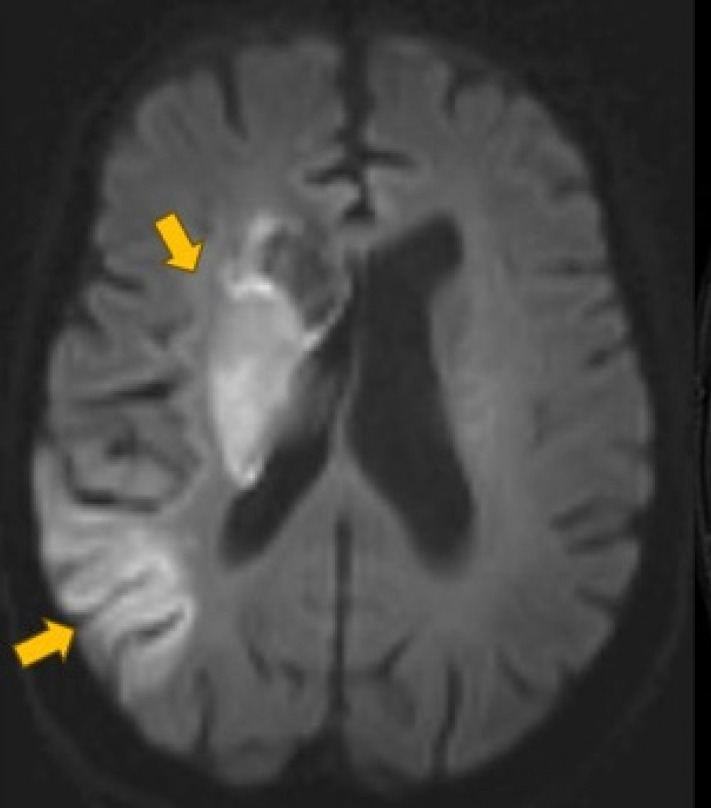

血管内治疗是目前治疗大血管闭塞引起的急性缺血性卒中的金标准治疗方法。尽管如此,严重的血管扭曲和颈动脉环的存在会阻碍手术的成功。我们报告一例83岁女性急性缺血性中风和极端扭曲,包括颈总动脉和颈内动脉连续环路,以及颈总动脉分叉串联血栓与M1段闭塞。随后,我们回顾了复杂取栓病例的技术管理方面的相关文献。血管内手术包括使用多种血管内工具通过极端的血管弯曲进行导航,使用输送装置促进手术的再灌注。手术过程中出现血管痉挛和颈内动脉袢拉直等问题。然而,成功的取栓使用适当的手术技术进行了讨论。

Endovascular therapy is the current gold standard treatment for the management of acute ischemic stroke from large vessel occlusion. Despite this, the presence of severe vascular tortuosity and cervical carotid loops can hinder the success of the procedure. We present a case of an 83-year-old female presenting with acute ischemic stroke and extreme tortuosity including common carotid artery and internal carotid artery consecutive loops, as well as a tandem common carotid artery bifurcation thrombus with an M1 segment occlusion. Subsequently, relevant literature is reviewed regarding the technical management of complex thrombectomy cases. The endovascular procedure involved navigating through extreme vascular tortuosity using multiple endovascular tools for optimal reperfusion using delivery devices to facilitate the procedure. Challenges such as vasospasm and straightening of an internal carotid artery loop occurred during the procedure. However, successful thrombectomy was performed using adequate procedural techniques discussed.